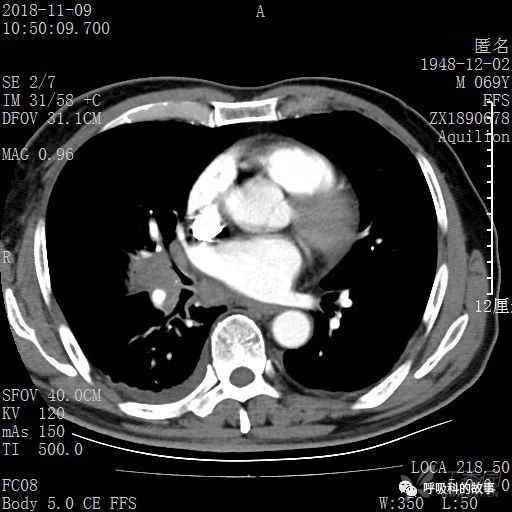

胸部增强CT示右肺门占位伴远端阻塞性肺炎,纵膈、右肺门、右侧颈根部、右侧腋下及肝门部肿大淋巴结。两侧胸腔少量积液。

肺窗CT